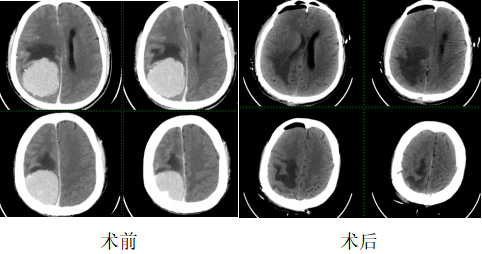

3月29日,株洲市人民医院神经外科联合麻醉科、输血科、检验科、重症医学科等多学科团队,成功完成该院首例储存式自体输血手术,为一名患有血供丰富巨大矢状窦旁脑膜瘤的患者实施择期开颅肿瘤切除术。手术全程精准把控麻醉风险、严控术中出血,顺利全切鹅蛋大小的颅内巨大肿瘤,患者术后神经功能显著改善,实现了该院储存式自体输血技术零的突破,复杂颅脑手术诊疗能力再攀新高。

而术前检查显示,颅内6cm×6cm×5cm的矢状窦旁脑膜瘤,体积堪比鹅蛋,且血供异常丰富,与颅内重要血管、矢状窦紧密粘连,如同“藤蔓缠绕”关键神经与血管,手术分离难度极大,此类手术被神经外科界称为“刀尖上的手术”,对医术和团队协作均是极限挑战。

手术历时6小时,成功全切肿瘤,出血量控制在600ml,回输术前贮存的400毫升自体血,全程未输注异体血,既有效缓解了血库紧张压力,又避免了异体输血带来的感染、免疫排斥等风险。

术后,患者转入重症医学科接受严密监护,恢复效果远超预期。术前因肿瘤压迫,左上肢肌力0级、左下肢肌力3-级,术后第二天左上肢肌力便恢复至2-3级,左下肢肌力恢复至3-4级,肢体活动能力大幅改善,意识清晰,顺利转出重症医学科,目前正稳步康复。